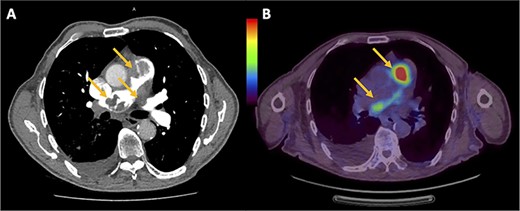

The patient was initially diagnosed with a large pulmonary embolus (PE) on imaging (Fig. 1A) was thrombolyzed and commenced on intravenous heparin infusion. Subsequently, endovascular clot retrieval was performed after failing thrombolysis, where the histopathology revealed PAIS. Transthoracic echocardiogram (TTE) showed severe pulmonary hypertension with a large mass in the pulmonary artery (PA) and right ventricle (RV) with partial occlusion of the RV outflow tract (RVOT). Positron emission tomography (PET) showed glucose avidity in the RVOT and pulmonary trunk (Fig. 1B) with no nodal or extrathoracic disease. The patient was also diagnosed with Heparin-induced thrombocytopaenia and thrombosis syndrome (HITTS) and was transitioned from heparin to fondaparinux. The patient also underwent preoperative radiotherapy.

(A) Chest computed tomography pulmonary angiogram showing intraluminal filling defects in the RVOT, pulmonary trunk and left PA. (B) PET showing the uptake of fluorodeoxyglucose within the RVOT and extending into both left and right PAs.